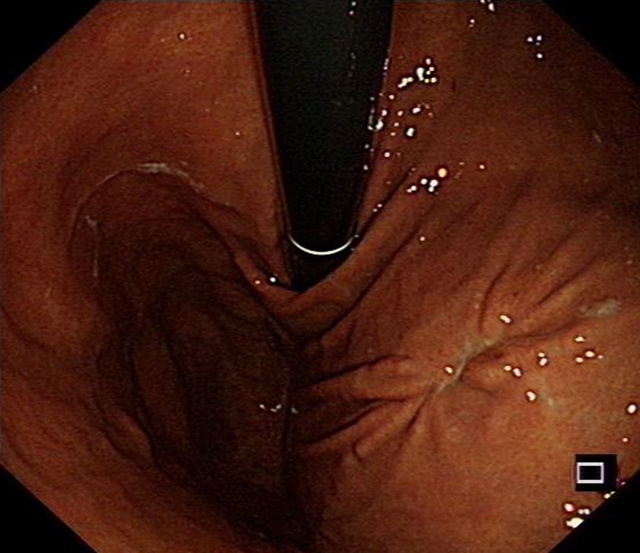

胃内大型黏膜下肿物破溃出现,箭头处为溃疡处

今年春节前夕,72岁的李婆婆被送入西南医科大学附属医院急诊科就诊时,呈休克状态,伴有呕血、黑便与贫血等症状。胃镜检查发现,她是因胃黏膜下肿物破溃出血才导致出现系列症状。

“切掉肿物,出血就会停止。”西南医科大学附属医院消化内科副主任汤小伟副教授介绍,李婆婆体内胃肿物直径约4厘米,邻近肝脏、胰腺等重要脏器。这类肿物常隐藏于黏膜之下,早期没有明显症状,倘若未能及时发现,就会悄悄增大导致疼痛、出血、梗阻,甚至危及生命。